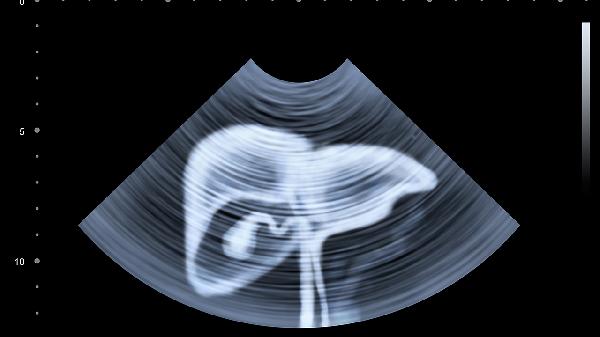

护肝关键在细节:用药前看说明书不良反应项;每半年查肝功能+超声;保持每天30克膳食纤维摄入;饮水不少于1500ml但不超过3000ml。记住,肝脏不需要特殊滋补,减轻负担就是最好的养护。从今天开始,给这个沉默的器官多一点温柔关照吧!